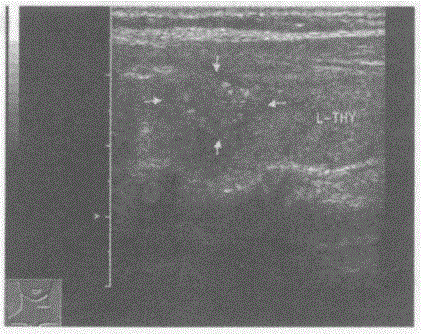

问题 临床资料:女,52岁,自述发现颈部肿物有压迫感半年余。 临床物理检查:甲状腺左叶可扪及一肿物,边界欠规整,活动度差。 超声综合描述:甲状腺形态、大小正常,左叶可见3.8cm×2.6cm低回声区,形态不规则,边界不清,呈锯齿状,内回声不均,内可见多个砂粒样强回声光点,CDFI:低回声区周边可见丰富动静脉血流信号,呈涡流频谱。见下图及彩图。 {图1} 超声提示:

选项 A.甲状腺癌 B.甲状腺腺瘤 C.结节性甲状腺肿 D.毒性甲状腺肿(原发性甲状腺功能亢进)

答案 A